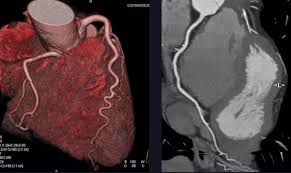

Coronary Angiogram

A CT Coronary Angiogram is a non-invasive imaging test that uses a CT scanner, and contrast dye to create detailed 3D pictures of your heart's arteries, revealing plaque, blockages, or narrowing (stenosis) that can cause heart problems like chest pain.

3D Vessel Analysis

Cardiac CT imaging is a non-invasive diagnostic technique that uses advanced computed tomography technology to create detailed images of the heart and coronary arteries. Our revolutionary CT scanner can capture the entire heart in just one rotation, providing exceptional image quality with minimal radiation exposure.

This advanced imaging technique allows for comprehensive evaluation of cardiac structures, coronary arteries, and heart function, enabling early detection and accurate diagnosis of various heart conditions.